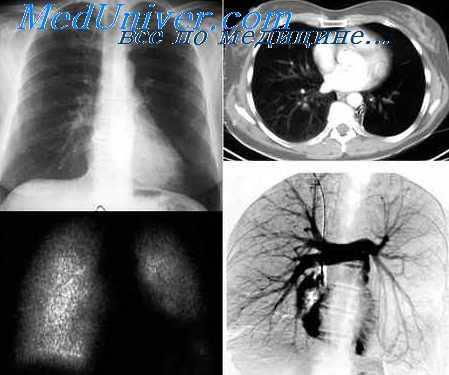

д) Лучевая диагностика перед выполнением процедуры:

• Для установления анатомических особенностей, возможных осложнений или противопоказаний к выполнению торакоскопического доступа выполняется КТ или КТА:

о Неоперабельное заболевание о Деформация грудной стенки

о Высокое стояние одного из куполов диафрагмы

о Близкое расположение сосудистых шунтов и области хирургического доступа